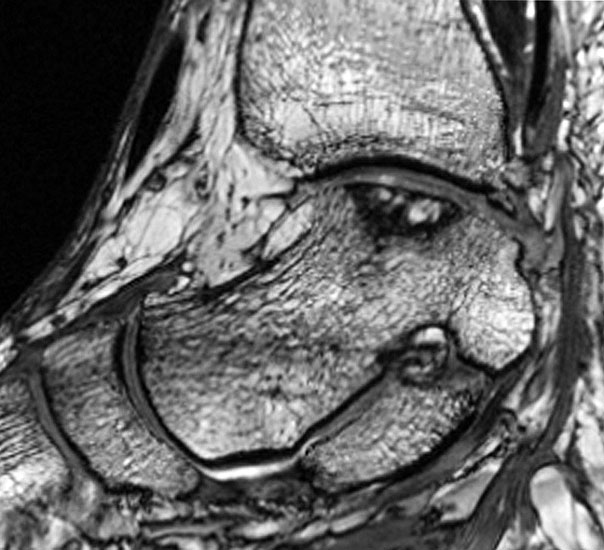

Im Laufe der Jahre hat sich die Magnetresonanztomographie (MRT) als sehr gute Option zur bildgebenden Diagnostik erwiesen. Die besonderen Vorteile liegen in der guten Beurteilbarkeit der Weichteilstrukturen und der Nichtinvasivität ohne Notwendigkeit der Verwendung von Röntgenstrahlen. Prinzipiell können alle geforderten Eigenschaften der Pathologie incl. der Veränderungen des subchondralen Knochens und des darüberliegenden Knorpels sowie der gelenkumgebenden Weichteilstrukturen visualisiert werden. Daher wird die MRT als Wichtigste anzufertigende Bildgebung angesehen 1720.

Die Standardsequenzen umfassen Fast-Spin-Echo (FSE) und Gradientenechosequenzen 22. Die Pulssequenzen umfassen typischerweise Protonendichte (PD) und fettunterdrückte Protonendichte Sequenzen (PD-FS) 17. In unserem eigenen Protokoll verwenden wir aktuell isotrope 3D-Gradientenechosequenzen (true FISP) (Abb. 3), protonendichte-fettunterdrückten Turbo-Spin-Echo-Sequenzen (PD-FS-TSE) (Abb. 4 und 5) und T1-gewichtete Spinechosequenzen (Abb. 6). Wichtig ist letztendlich die räumliche Auflösung als Funktion der Schichtdicke, dem Blickfeld (FOV) und der Bildmatrix 17.

Die Verwendung von intravenösem oder intraartikulärem Kontrastmittel kann die Diagnostik und Einteilung in eine Klassifikation erleichtern. Nach intravenöser Kontrastmittelgabe spricht die Aufnahme des Kontrastmittels im Interface zwischen osteochondralem Fragment und dem Fragmentbett für Granulationsgewebe im Grenzspalt. Wenn diese Kontrastmittelaufnahme in einer T2-Wichtung nicht stattfindet und das Signal unverändert bleibt, spricht dies für Flüssigkeit im Interface, was eine instabilere Situation bedeuten würde 23. Ebenso kann der Vaskularisierungsgrad des Fragmentes und damit die Vitalität abgeschätzt werden, dies ist allerdings nur eingeschränkt möglich 23. Bei intraartikulärer Kontrastmittelgabe kann die Integrität des Knorpels und der Dissektionsgrad des osteochondralen Fragmentes besser abgeschätzt werden. Ebenso kann eine Verbindung von subchondralen Zysten zum Gelenk beurteilt werden 19.

Trotz der vielfältigen Möglichkeiten der MRT ist die Beurteilung des Ausmaßes der knöchernen Beurteilung der Läsion teilweise schwierig. Die Ausdehnung des Knochenmarködems führt dabei manchmal zu einer Überschätzung der Läsionsgröße 24.